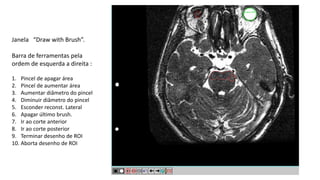

Janela “Draw with Brush”.

Barra de ferramentas pela

ordem de esquerda a direita :

1. Pincel de apagar área

2. Pincel de aumentar área

3. Aumentar diâmetro do pincel

4. Diminuir diâmetro do pincel

5. Esconder reconst. Lateral

6. Apagar último brush.

7. Ir ao corte anterior

8. Ir ao corte posterior

9. Terminar desenho de ROI

10. Aborta desenho de ROI